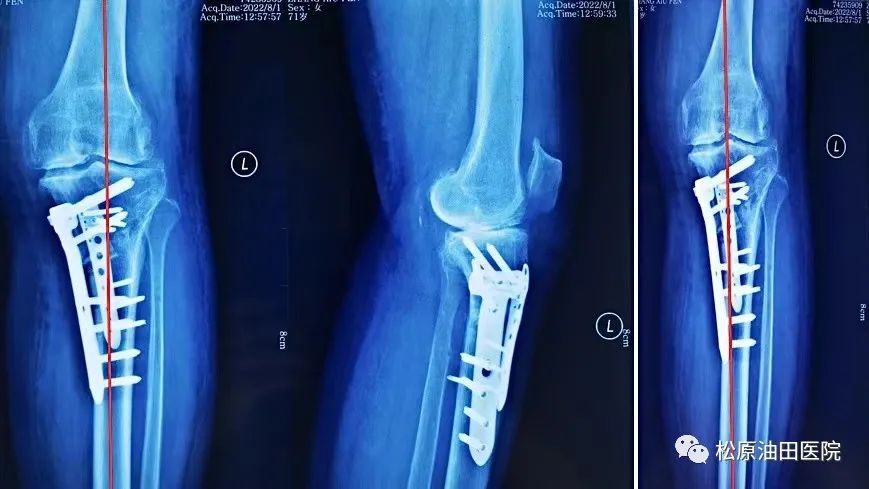

据悉,今年松原吉林油田医院放射线科引进开展负重位下肢全长的影像系统检查项目,它可以全面观察骨与关节的形态、密度的改变,负重位真实对生理角度、畸形角度、力线进行测量,为下肢畸形矫正、植骨术,尤其是膝关节矫形术或关节置换术前、术后提供了有力的测量依据。在此基础上,医院骨三科主任冯宪发团队在松原率先开展了不换膝关节“微创保膝”治疗新技术,此技术为国内领先技术,达到了推迟或不换膝关节治疗膝关节骨性关节炎。

到目前,松原市内外已有11位患者享得了新技术带来的福利,深得患者的好评。